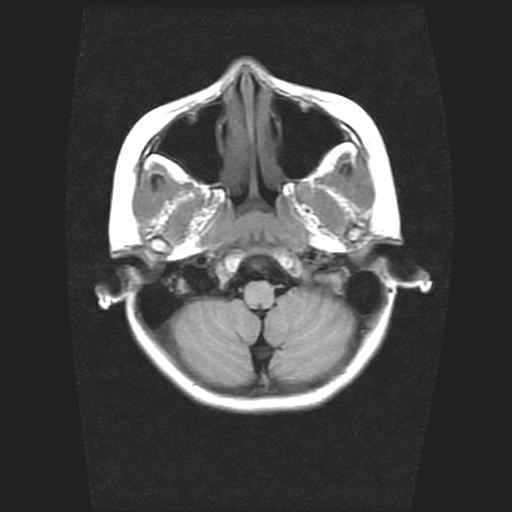

9岁女孩,三岁时诊断为癫痫,一直服丙戊酸钠,现患者一般情况良好,家长复查核磁片,看能否停药..

巨脑回